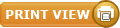

Here's another figure taken from Lou et al 2008 again showing an increase in peak Pes during an apnea. Peak Pes was noted to be less than my example. They also measured abdominal muscle activity (shown as EMGab). You can easily see an increase in muscle activity and Pga swings during expiration for the last three efforts during the apnea. I quote "The EMGab signal was silent at the beginning of an apnoea and became active during the expiratory phase, further supporting the concept that expiratory muscle contraction causes an increase in end expiratory Poes." I actually don't believe they mean end-expiratory Pes, but probably peak Pes.

Also "contraction of the abdominal muscles as evidenced by the rectus muscle EMG, is the cause of increasing end expiratory Poes."